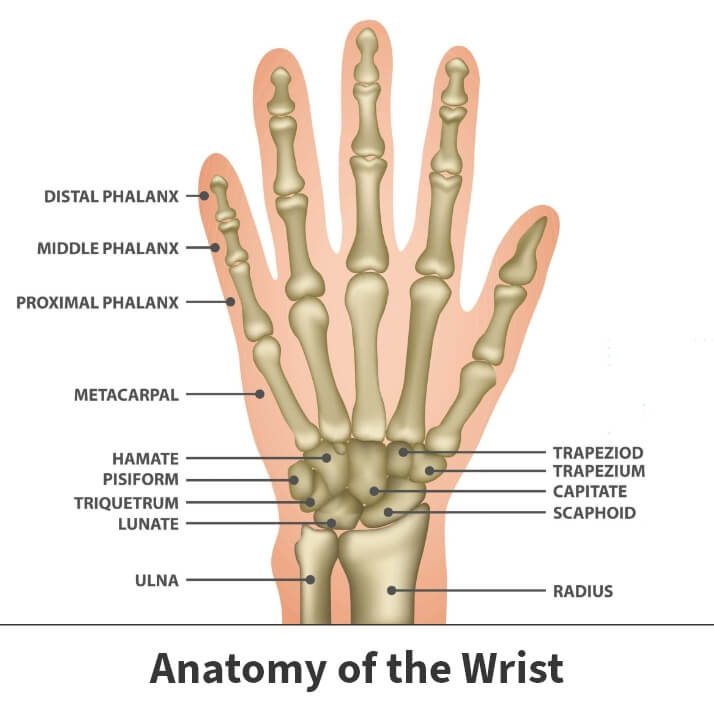

List showcases captivating images of what does a broken wrist look like pictures galleryz.online

what does a broken wrist look like pictures